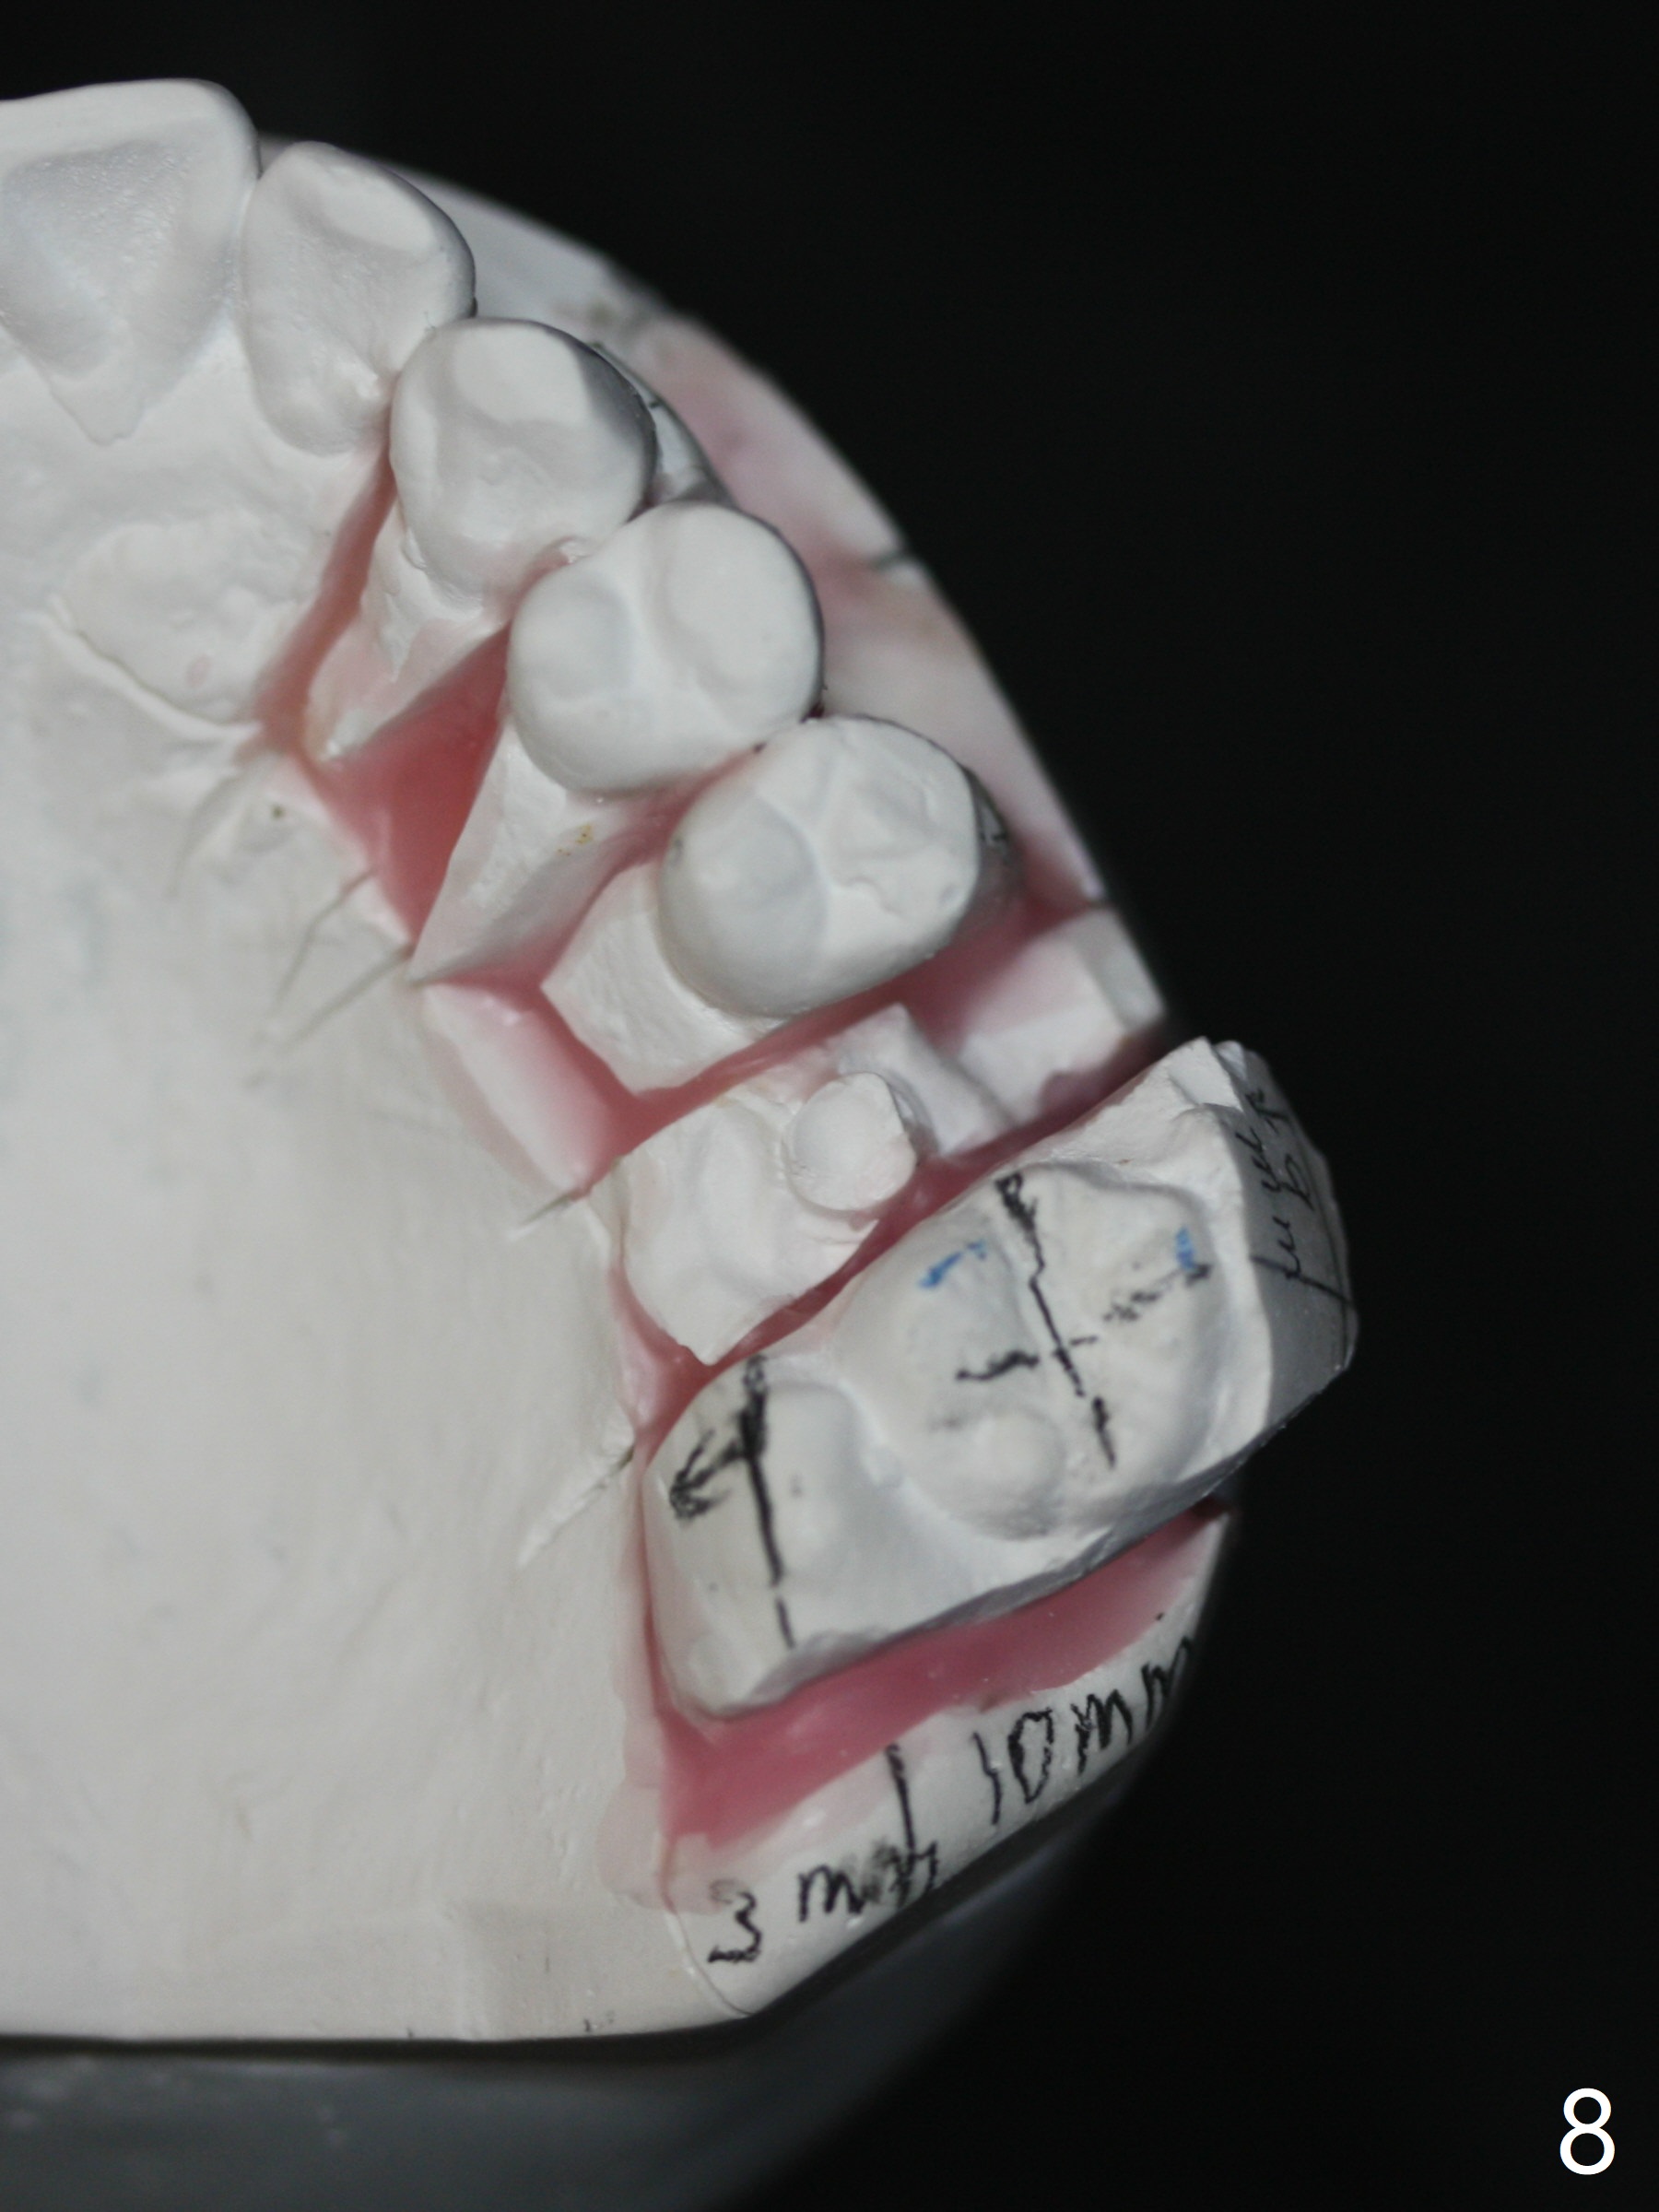

A 45-year-old man with normal facial profile (Fig.1-4) and malocclusion confined to UL quadrant (Fig.5-6) agrees with comprehensive orthodontic treatment. The implant threads at UL6 remain exposed 2 years 4 months postop. Thread exposure should disappears by distalizing UL5 and extruding UL8. Although upper wire sequence should be able to the limited malocclusion, extrusion of UL8 may use the lower arch as an anchor (elastic once a rectangular wire is installed, Fig.7,8).